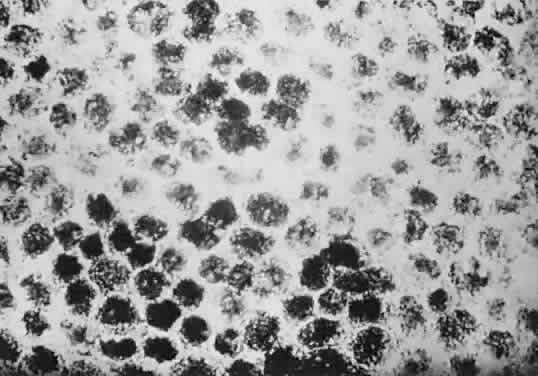

Histologically, the involved RPE cells are taller and contain a greater concentration of pigment granules (which may be enlarged) than normal RPE (Fig. 21). The overlying retina has been shown to be unaffected in one patient.171

Fig. 21. Flat-mount preparation of congenital grouped pigmentation of the retina shows a greater concentration of pigment granules within the area corresponding to the lesions. (Courtesy of Dr. Jerry Shields)